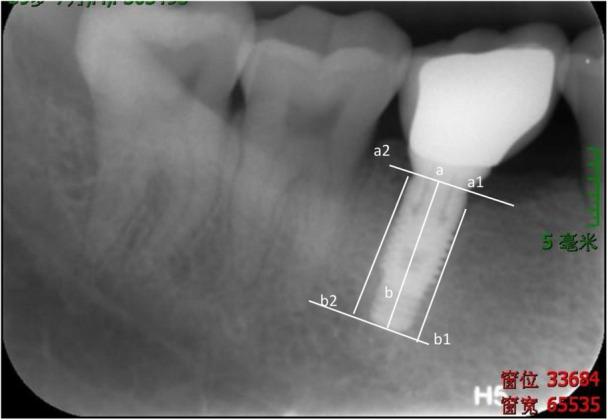

MATERIAL AND METHODS

The participants needing the restoration of a single missing mandibular molar were randomized into immediate restoration (IR) and conventional restoration group (CR). All eligible patients were recalled for collecting peri-implant crevicular fluid (PICF) samples according to the scheduled follow-up time point during osseointegration and functional loading. Detection of receptor activator of nuclear factor-KB ligand, osteoprotegerin, and cathepsin K in PICF was conducted to statistically analyze their difference between IR and CR groups.

材料与方法

将需要修复单个缺失下颌磨牙的参与者随机分为即刻修复组(IR)和传统修复组(CR)。在骨整合和功能加载期间,根据预定的随访时间点召回所有符合条件的患者,以收集种植体周围龈沟液(PICF)样本。对PICF中的核因子-κB受体激活剂配体、骨保护素和组织蛋白酶K进行检测,以统计分析IR组和CR组之间的差异。